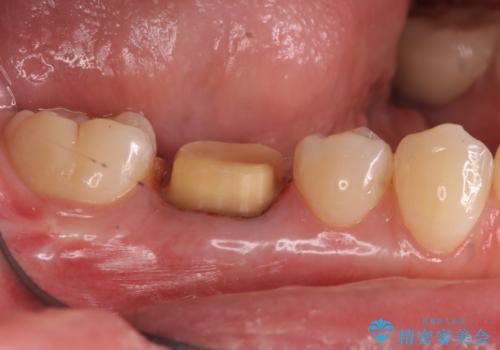

樹脂をセラミックにしたい ジルコニアクラウンでの治療

- 樹脂をやり替えたいとのことで来院されました。

特に大きな虫歯もありませんでしたが、残った歯が薄かったためクラウンでの修復処置を行いました。

- 右下6 仮歯+ジルコニアクラウン 11,000円+110,000円費用は治療当時の料金となります

インレーにすると残った歯が薄くなってしまう場合は術後の破折リスクが高いためクラウンで修復することがあります。